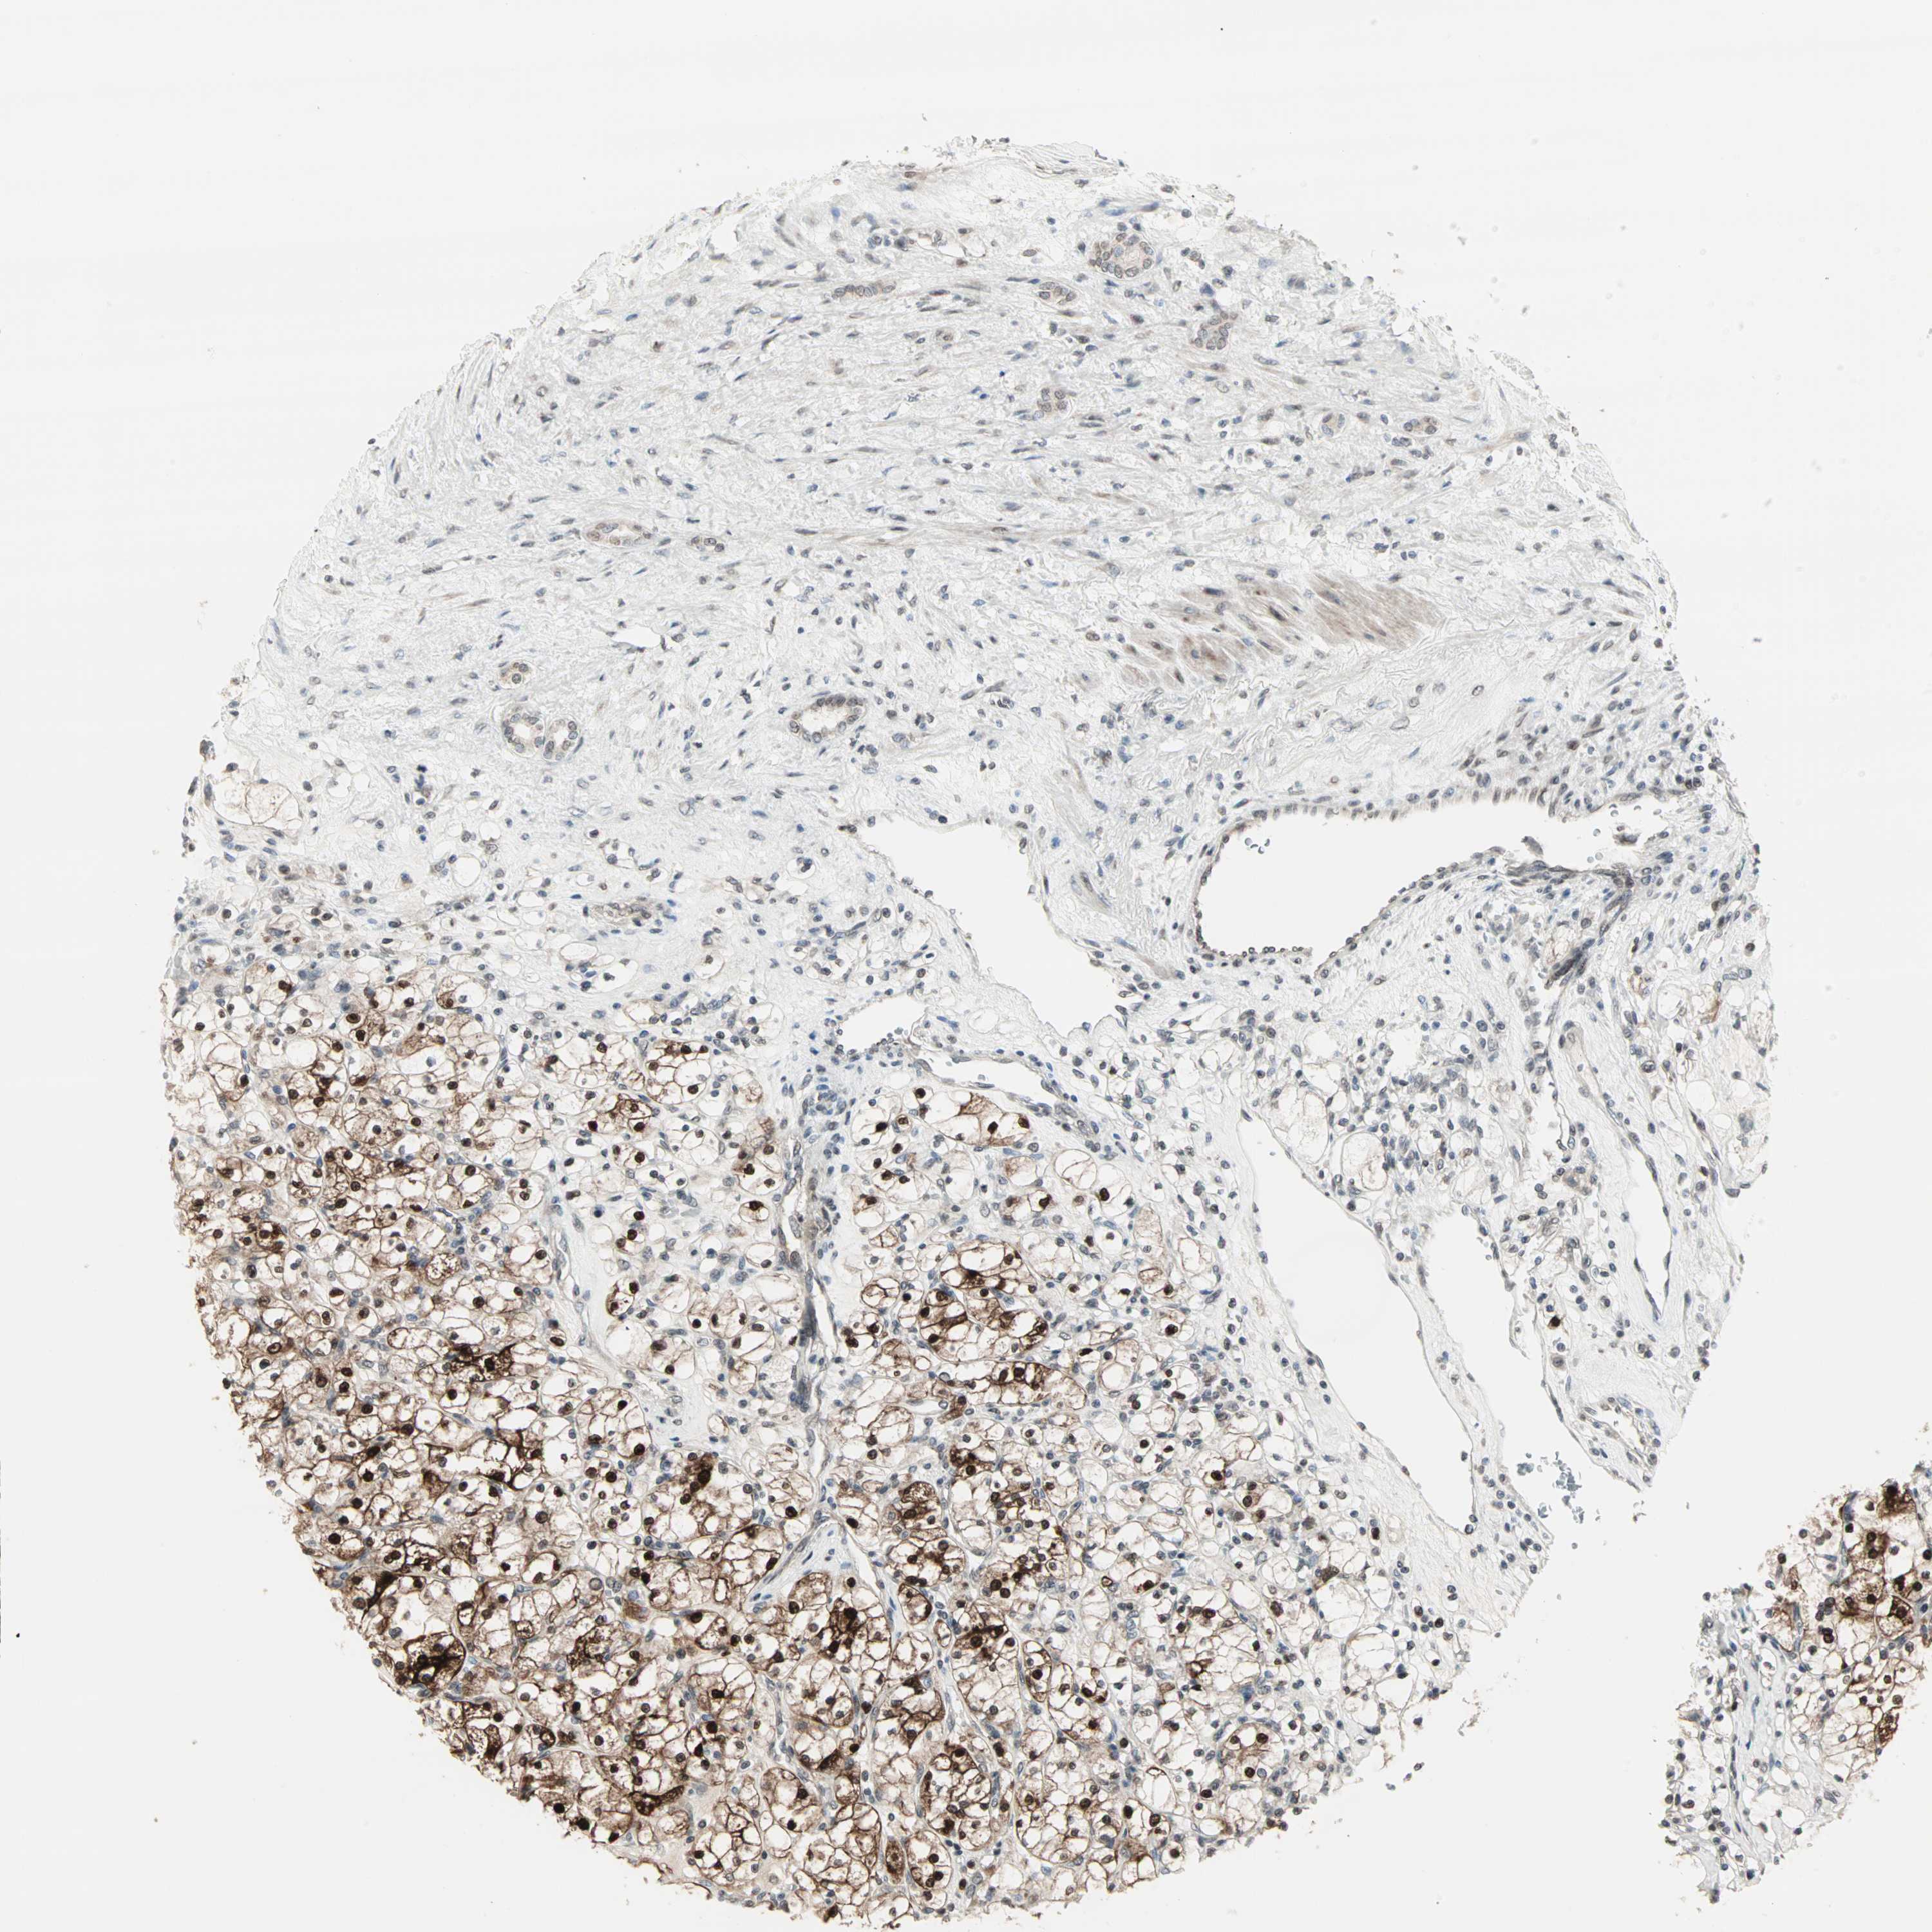

KIDNEY RENAL PAPILLARY CELL CARCINOMA (TCGA) - Interactive survival scatter ploti

CBLC is potential prognostic, high expression is favorable in Kidney Renal Papillary Cell Carcinoma (TCGA)

: 4.83